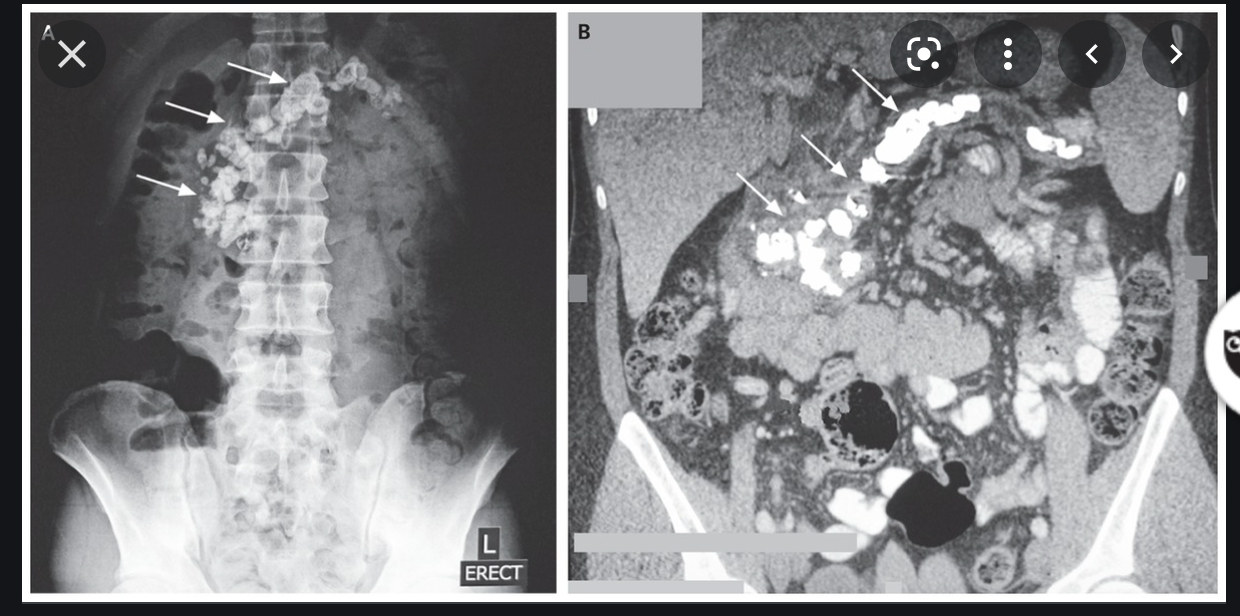

Complications of Chronic Pancreatitis

Generalised atrophy of body and tail of the pancreas. Diffuse parenchymal calcification with main pancreatic duct dilated throughout its course with a beaded appearance reaching up to 10mm in diameter. Multiple intraductal calculi are present, the largest measuring 10 mm in the pancreatic head. This stone is obstructing the main pancreatic duct resulting in ductal dilatation. No hypoenhancing pancreatic parenchymal lesions. No peripancreatic fat stranding or localised collections. No radio-opaque stones in the gallbladder, cystic duct, or common bile duct. No intrahepatic biliary duct dilatation.

Case Discussion

When presenting with an episode of abdominal pain, this patient underwent an ultrasound of the abdomen which revealed features of chronic calcific pancreatitis. However, due to the suboptimal acoustic window, a CT scan was recommended to rule out any pancreatic inflammation or neoplasm. The chronic inflammatory changes result in reduction in volume of pancreatic parenchyma with only a ghost of the gland remaining in the latter stages. These patients are more prone for neoplasms and have to be watched closely.